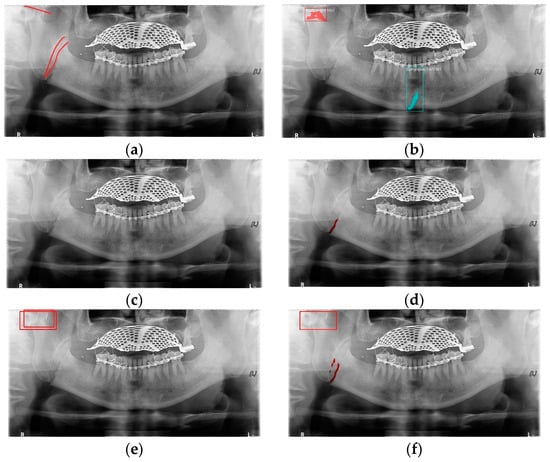

In Table 6, the parameters used for training are indicated, and in Figure 11, Figure 12 and Figure 13, the results of the doctor’s diagnosis, Mask R-CNN, YOLOv4, U-Net, LAT YOLOv4, and U-Net withYOLOv4 are compared. Figure 11 illustrates fractures in the angle and condylar regions, and in Mask R-CNN, the symphysis is misdiagnosed as a fracture. In Figure 12, the Mask R-CNN misdiagnoses the symphysis as a fracture, the result of the fact that the YOLOv4 module has better performance detecting angle fractures rather than does the LAT YOLOv4, as shown in Figure 12c,e. In short, the LAT-processed image does not always have the advantage of better revealing fractures compared with the normal panoramic radiograph.

Figure 11.

The comparison of mandibular fracture detection: (a) oral and maxillofacial radiologist, (b) Mask R-CNN (with colored polygons and boxes), (c) YOLOv4, (d) U-Net (with a red line), (e) LAT YOLOv4 (with red boxes), and (f) U-Net with LAT YOLOv4 (with a red box and lines).

Figure 12.

The comparison of mandibular fracture detection: (a) oral and maxillofacial radiologist, (b) Mask R-CNN (with colored polygons and boxes), (c) YOLOv4 (with a red box), (d) U-Net (with a red line), (e) LAT YOLOv4, and (f) U-Net with LAT YOLOv4 (with a red line).

Figure 13.

The comparison of mandibular fracture detection: (a) oral and maxillofacial radiologist, (b) Mask R-CNN (with colored polygons and boxes), (c) YOLOv4 (with a red box), (d) U-Net (with red lines), (e) LAT YOLOv4 (with red boxes), and (f) U-Net with LAT YOLOv4 (with a red box and lines).

In Figure 13, the ramus is misdiagnosed as a fracture. Therefore, Mask R-CNN had the lowest precision score because the misdiagnosis rate was higher than that of the other modules (Figure 16). The YOLO module has a low misdiagnosis rate, while the ‘undiagnosis’ rate is high; therefore, the F1 score is low owing to the ’undiagnosis’ rate. As shown in Figure 11, Figure 12 and Figure 13, YOLOv4 and LAT YOLOv4 have strong advantages over location information; therefore, they tend to detect well in the condyle region, that is, the side fracture, while they tend to detect poorly in the symphysis, body, and angle regions, where location information is ambiguous. Unlike Mask R-CNN and YOLO, U-Net is an image segmentation deep learning network, not an object detection deep learning network and labels mandibular fractures. U-Net marks fractures as lines on the label during training; however, it is difficult to label dislocated fractures, such as condyle fractures (Figure 11). Therefore, in the U-Net module, the side fracture was not diagnosed or misdiagnosed, and the precision-recall score was lower than that of the YOLO modules. It was judged that if the two deep learning networks are used together, the shortcomings of YOLO and U-Net complement each other and help improve mandibular fracture performance. In the proposed module, duplicate boxes that occurred in LAT YOLOv4 were removed before merging with the U-Net. In the proposed U-Net with LAT YOLOv4, the precision score was reduced; however, many ‘undiagnoses’ were eliminated; therefore, the recall score was increased, and it can be observed that the overall F1 score improved the performance by more than 90%.